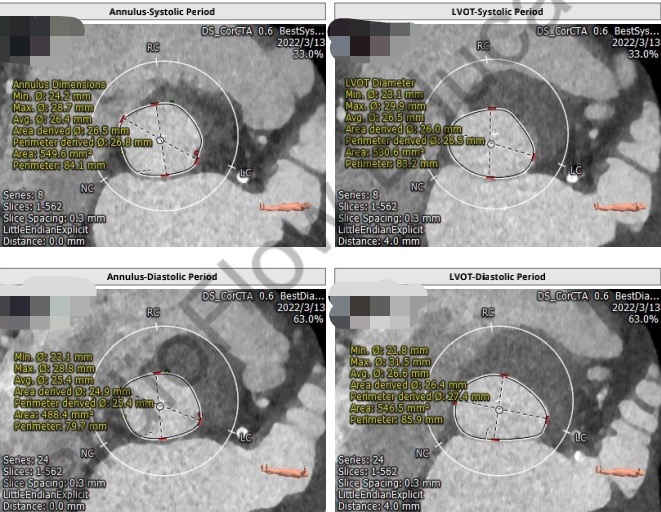

钟炜主任指出:患者为三叶式主动脉瓣纯反流病例,瓣环周长84.1mm,平均径26.4mm。LVOT周长83.2mm,平均径26.5mm。瓦氏窦瘤样扩张,窦宽大于50mm,窦管结合部几近消失,锚定能力严重不足,该患者选择TAVR手术,瓣膜支架能否在这么大的窦瘤和瓣环内固定是非常有挑战的,通过详细分析CT结果,如果能将瓣膜支架放在主动脉瓣下4-5mm,应该能够充分利用径向支撑力起到固定作用,为了精准释放瓣膜支架,建议经颈动脉入路。

CT分析

主动脉根部解剖: